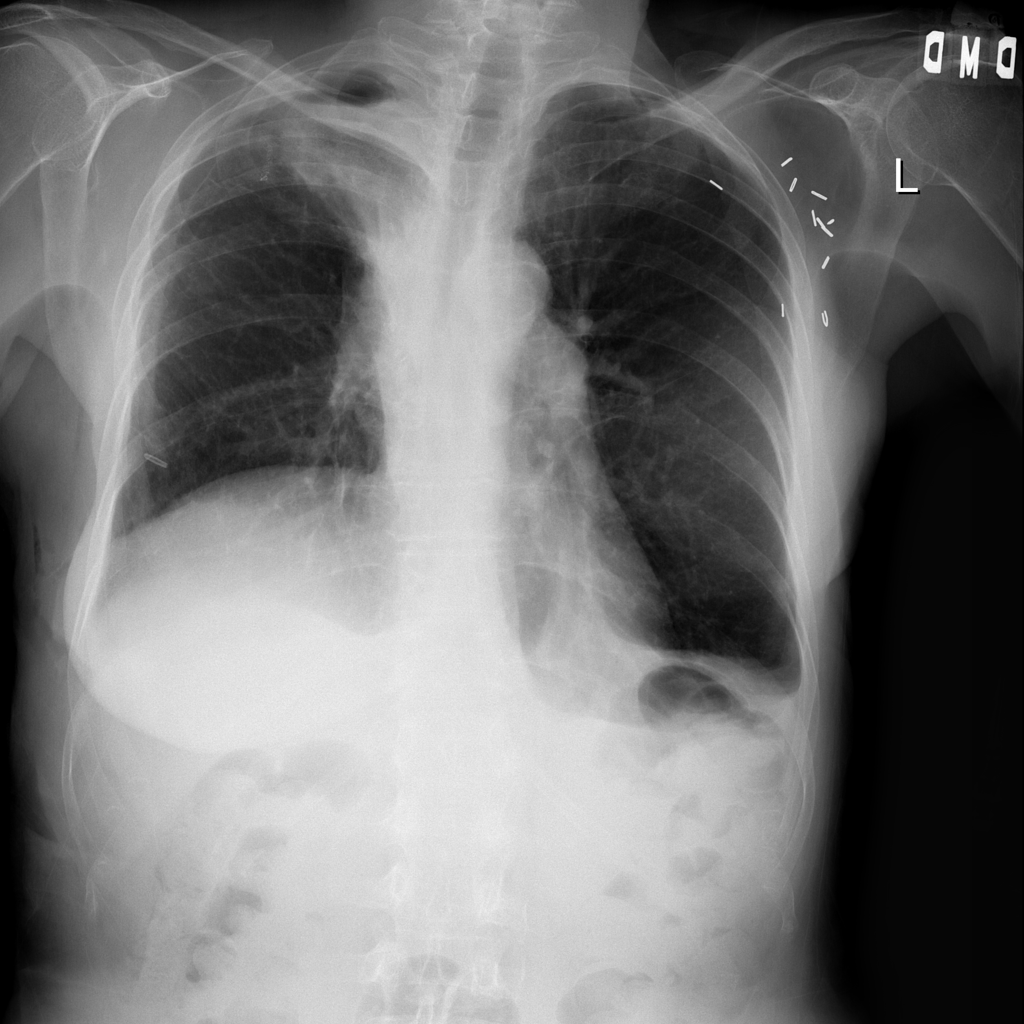

PAT-40F9 · IMG-004Effusion

PAT-40F9 · IMG-004

PA